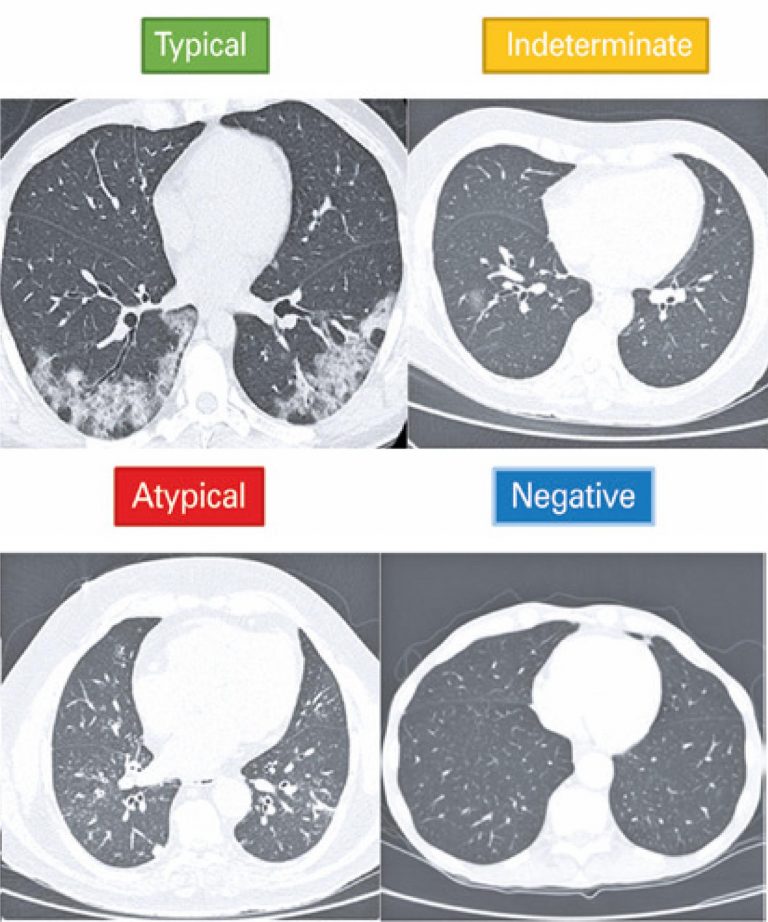

ABSTRACT Objective To compare inter-rater reliability, diagnostic accuracy, and extension of pulmonary involvement in children with suspected COVID-19 submitted to supine or supine and lateral decubitus computed tomography imaging. Methods Retrospective study carried out between March 2020 and March 2021 with patients submitted to reverse transcription-polymerase chain reaction testing and chest computed tomography. Patients were divided into two groups: supine or supine and lateral decubitus imaging. Standardized reporting systems of computed tomographic findings in COVID-19 and chest computed tomography score […]

Chest computed tomography in the diagnosis of COVID-19 in patients with false negative RT-PCR

DOI: 10.31744/einstein_journal/2021AO6363

ABSTRACT Objective To evaluate the role of chest computed tomography in patients with COVID-19 who presented initial negative result in reverse transcriptase-polymerase chain reaction (RT-PCR). Methods A single-center, retrospective study that evaluated 39 patients with negative RT-PCR for COVID-19, who underwent chest computed tomography and had a final clinical or serological diagnosis of COVID-19. The visual tomographic classification was evaluated according to the Consensus of the Radiological Society of North America and software developed with artificial intelligence for automatic detection […]

Keywords: Coronavirus infections; Reverse transcriptase polymerase chain reaction; Tomography, x-ray computed

Differential diagnoses of acute ground-glass opacity in chest computed tomography: pictorial essay

DOI: 10.31744/einstein_journal/2021RW5772

ABSTRACT Ground-glass opacity is a very frequent and unspecified finding in chest computed tomography. Therefore, it admits a wide range of differential diagnoses in the acute context, from viral pneumonias such as influenza virus, coronavirus disease 2019 and cytomegalovirus and even non-infectious lesions, such as vaping, pulmonary infarction, alveolar hemorrhage and pulmonary edema. For this diagnostic differentiation, ground glass must be correlated with other findings in imaging tests, with laboratory tests and with the patients’ clinical condition. In the context […]

Keywords: Coronavirus infections; COVID-19; Diagnosis, differential; Pandemics; SARS-CoV-2; Thorax/diagnostic imaging; Tomography, x-ray computed